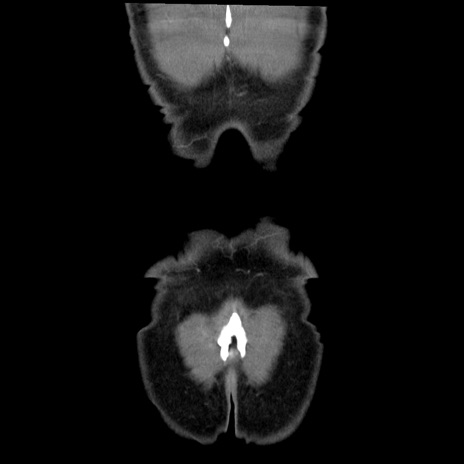

横断像